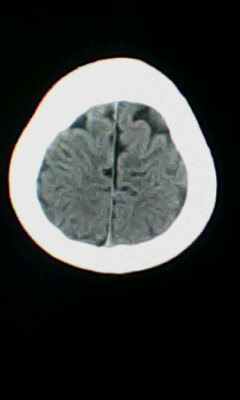

颅脑ct轴位平扫颅内未见明确异常。

颅脑ct轴位平扫颅内未见明确异常,建议mri。